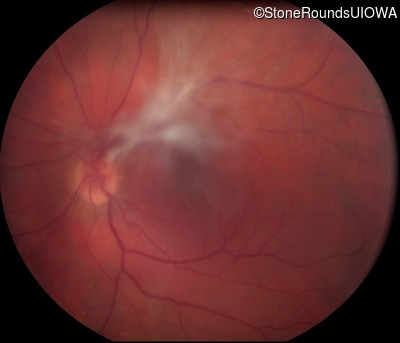

Visit at age: 33 years

Fundus Photography - Left - 20/200 sc

Exemplar